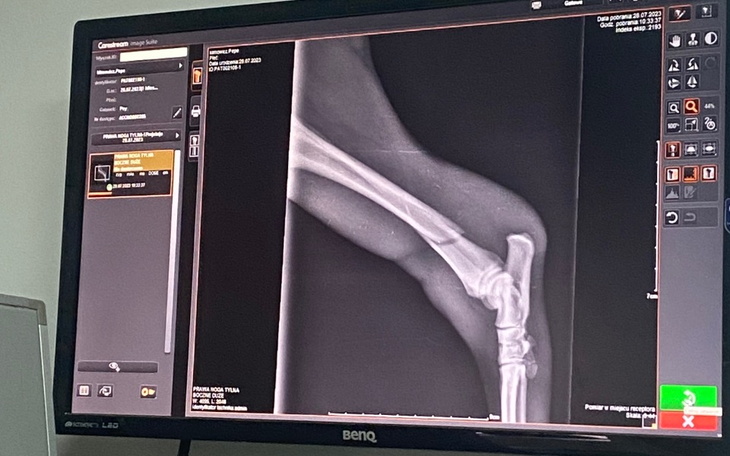

Mam na imię Pepe, mam pół roku. Wczoraj podczas zabawy niefortunnie upadłem i połamałem kość w tylnej łapce. Żebym mógł dalej biegać i cieszyć się swoim pieskim życiem potrzebna mi operacja zespalająca pęknięta kość i czterotygodniowa rekonwalescencja. Jesteśmy wdzięczni za każdy wpłacony pieniądz. Pomóż mi wrócić do pełnej sprawności.